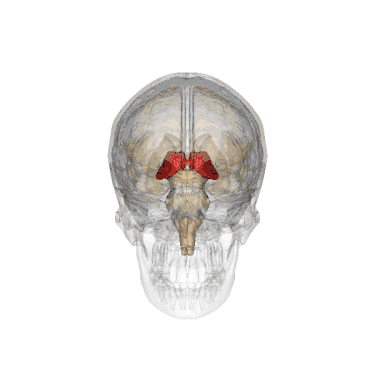

Таламус або талямус (лат. thalamus dorsalis, від грец. θάλαμος — «кімната», «шлюбне ліжко») — ділянка сірої речовини у верхній частині проміжного мозку хордових тварин. Таламус є симетричною, розміщеною обабіч міжпівкульної серединної лінії, структурою, складеної з двох однакових половинок. Він розміщений між структурами великого мозку, зокрема корою, та структурами середнього мозку. Серединна поверхня обох половинок таламуса є водночас верхньою боковою стінкою третього шлуночка головного мозку.

![]() Таламус в проекції черепа | |